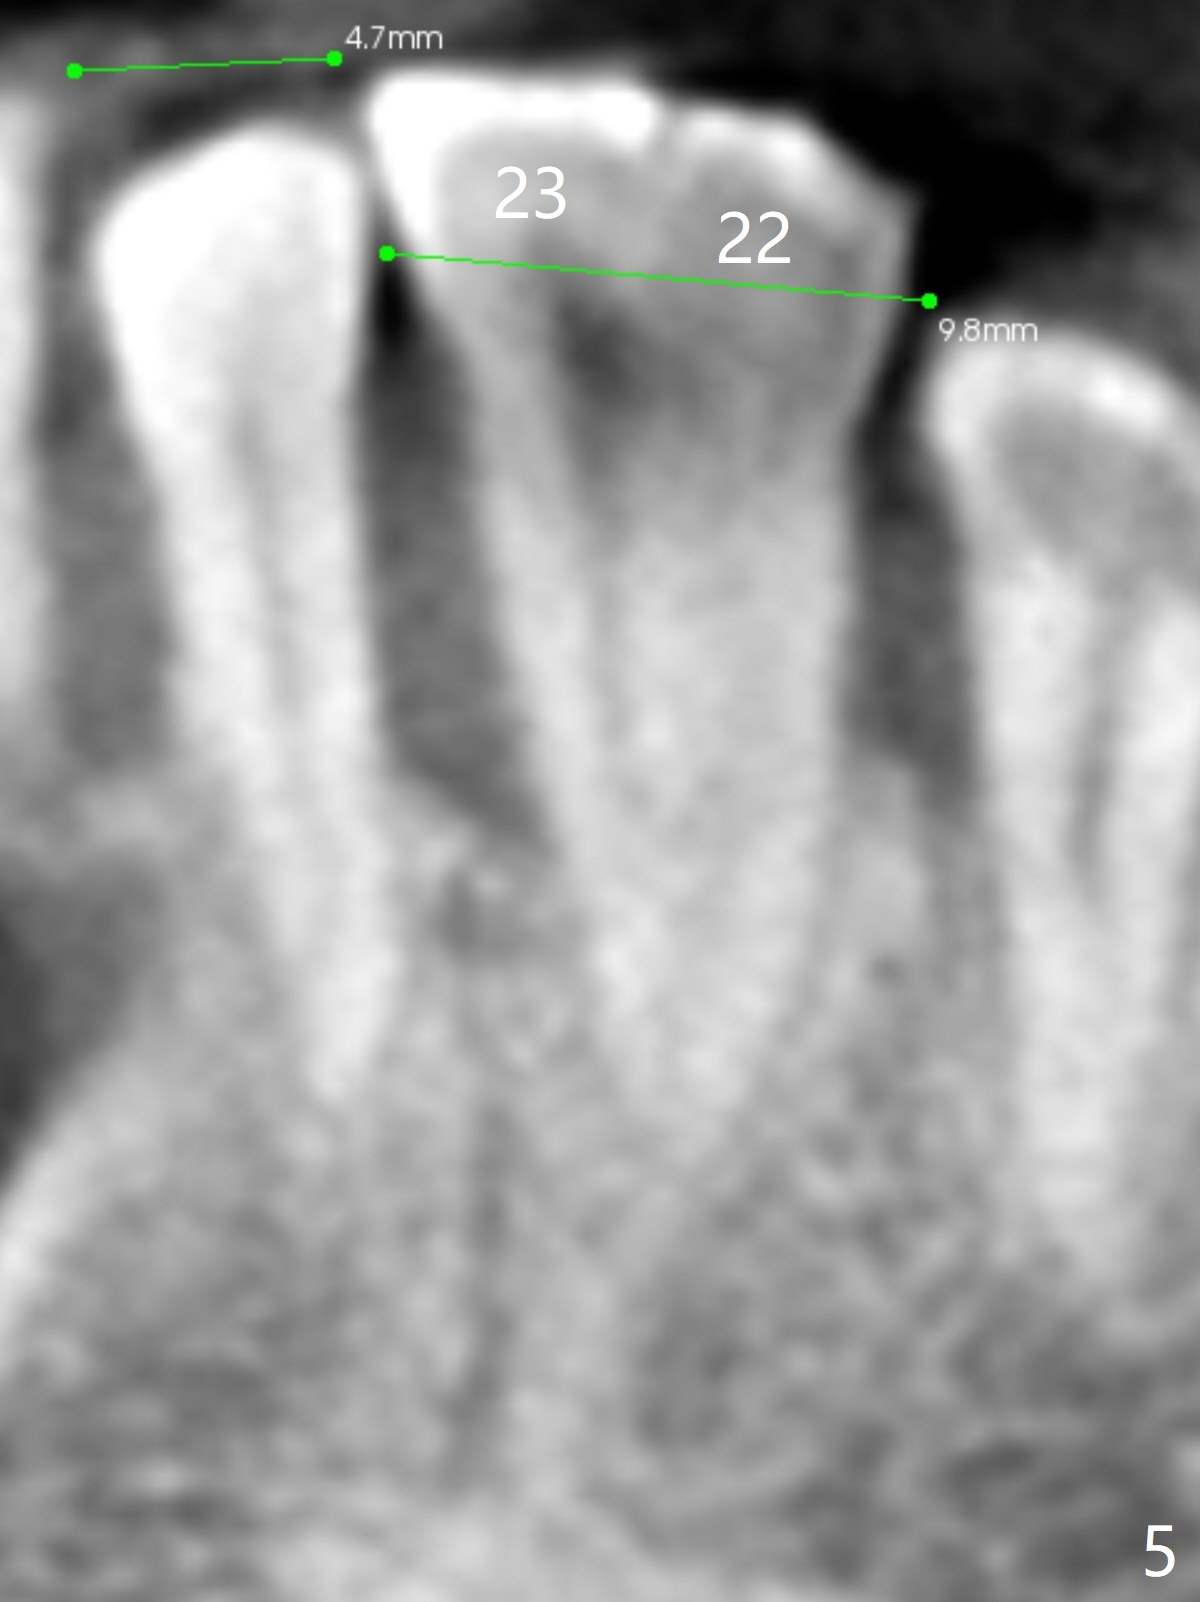

In fact, #22/23 mesiodistal width is ~ twice of that of an incisor (Fig.5). It is apparently more proper to place two smaller 1-piece implants (Fig.6) or a larger 2-piece one (Fig.7,8 (change to tissue-level one)).